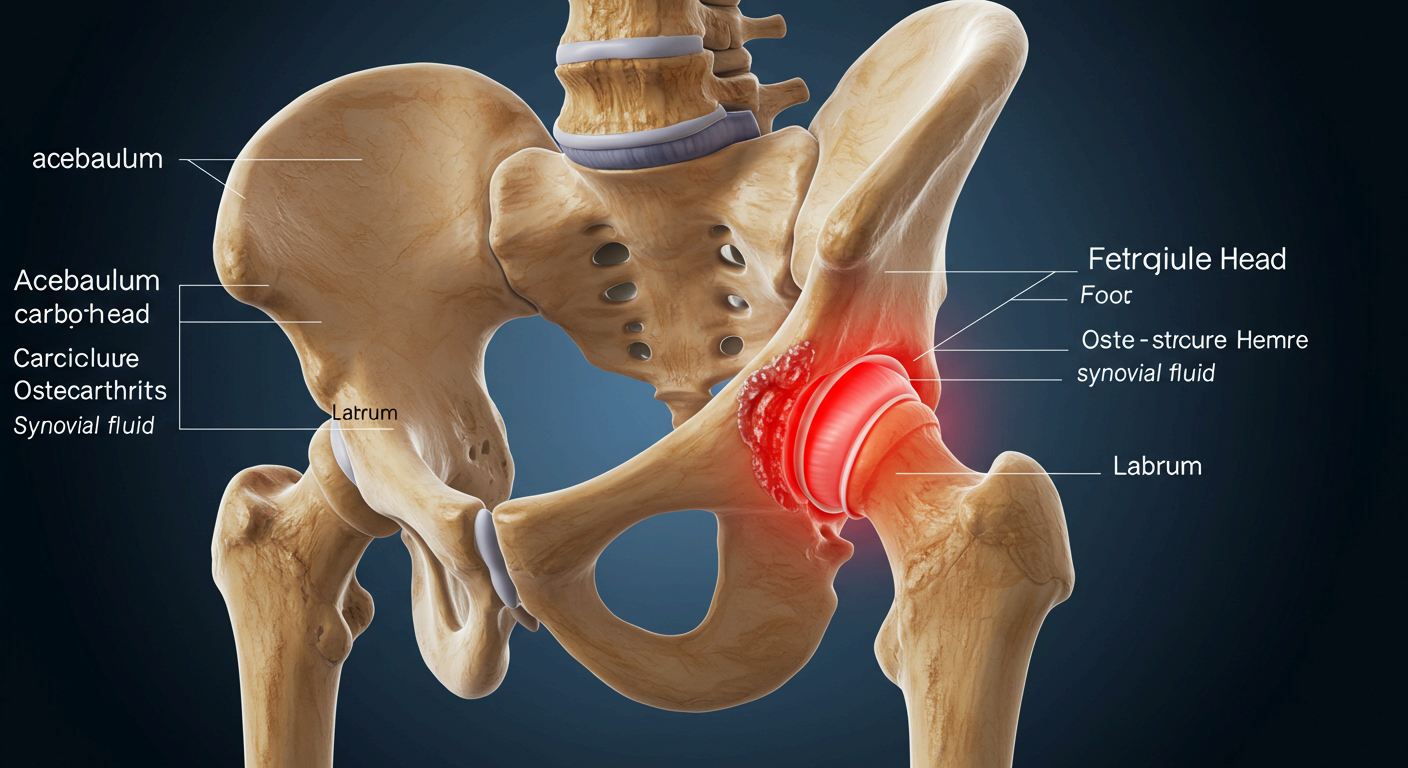

📌 고관절 충돌 증후군 (FAI)

- 대퇴골두와 비구가 부딪히는 구조적 이상으로 통증 유발

- 주로 젊은 운동선수나 활동량이 많은 사람에게 발생

📌 퇴행성 고관절염

- 고관절 연골이 닳아 없어지며 뼈와 뼈가 직접 마찰됨

- 50대 이상에서 흔하며, 통증·운동 제한·관절 소리 등이 특징

📌 대퇴골두 무혈성 괴사

- 혈액 공급 부족으로 뼈 조직이 괴사되어 통증 유발

- 음주, 스테로이드 과다 사용 등도 원인이 될 수 있음